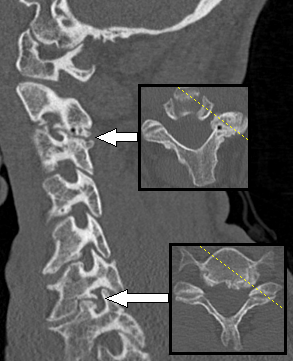

- تعد فحوصات التصوير بالرنين المغناطيسي والتصوير المقطعي المحوسب مفيدة في تشخيص الألم ولكنها ليست نهائية بشكل عام ويجب أخذها في الاعتبار مع الفحوصات الجسدية والتاريخ.[5]

جراحة تخفيف الضغط: يمكن إجراء جراحة العمود الفقري من الأمام والخلف. يختلف النهج باختلاف الموقع وسبب ضغط الجذر. بشكل عام ، تتم إزالة النبتات العظمية وأجزاء من القرص الفقري.[9]

جراحة الدمج : تُجرى عندما يكون هناك دليل على عدم استقرار العمود الفقري أو سوء المحاذاة. يختلف استخدام الأجهزة (مثل البراغي العنقية) في جراحات الاندماج عبر الدراسات.[8]